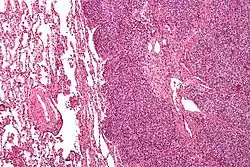

Micrograph of metastatic Ewing sarcoma (right of image) in normal lung (left of image). PAS stain.

Micrograph of a metastatic Ewing sarcoma with the characteristic cytoplasmic clearing on H&E staining, which was showing to be PAS positive

The definitive diagnosis is based on histomorphologic findings, immunohistochemistry and molecular pathology.

Ewing sarcoma is a small-blue-round-cell tumor that typically has a clear cytoplasm on H&E staining, due to glycogen. The presence of the glycogen can be demonstrated with positive PAS staining and negative PAS diastase staining. The characteristic immunostain is CD99, which diffusely marks the cell membrane. However, as CD99 is not specific for Ewing sarcoma, several auxiliary immunohistochemical markers can be employed to support the histological diagnosis.[23] Morphologic and immunohistochemical findings are corroborated with an associated chromosomal translocation, of which several occur. The most common translocation, present in about 90% of Ewing sarcoma cases, is t(11;22)(q24;q12),[24][25] which generates an aberrant transcription factor through fusion of the EWSR1 gene with the FLI1 gene.[26]